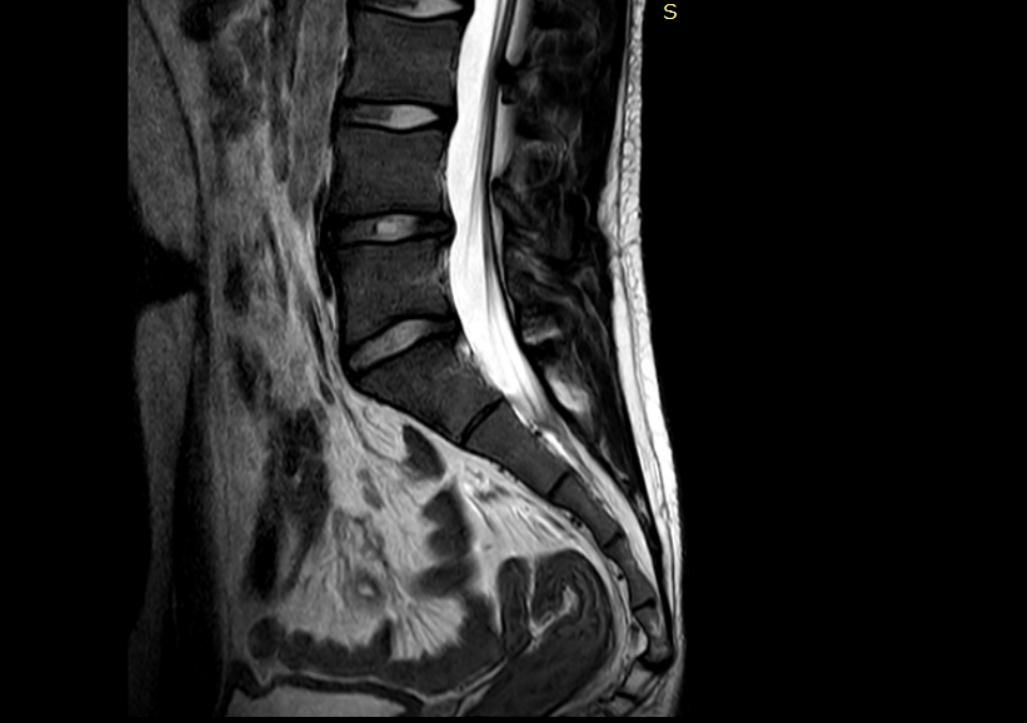

제가 7월28일에 어깨 수술이후 골반쪽이 계속 아프더라구요 그래서 엠알아이 찍어봤는데 꼬리뼈 돌출이됬습니다 그 어깨 수술이후 자세 불균형 때문에 그럴수가 있나요 ? 그리고 동그라미 한 저 허리쪽은 왜 하얀건가여ㅛ

동그라미 친 허리 쪽의 "하얀 부분은 MRI에서 뇌척수액(CSF)" 으로, 신경을 싸는 정상 구조입니다.

다만  직접적인 원인이라기보다는 유발·악화 요인 으로 보는 게 정확해요. 어깨 수술 후에는 통증 때문에 한쪽으로 몸을 기울이거나, 보호 자세로 오래 지내게 되는데요. 그러면 척추–골반 정렬이 틀어지고, 특히 오래 앉아 있거나 비스듬히 기대는 습관이 생기면 꼬리뼈에 지속적인 압력이 가해질 수 있습니다. 원래 약간의 구조적 문제나 유연성 문제가 있던 상태라면, 이런 자세 변화로 꼬리뼈 돌출이나 통증이 드러나거나 심해질 수 있어요. 동그라미 친 허리 쪽이 하얗게 보이는 건 정상적인 MRI 소견입니다. 이건 병변이 아니라 척수액(뇌척수액)이에요. MRI 종류 중 T2 영상에서는 물 성분이 하얗게 보이는데, 척수 신경을 둘러싼 액체가 그렇게 보이는 겁니다. 즉, 하얀 것 자체는 문제 아닙니다. 지금 단계에서는 자세 교정, 골반·코어 재활, 앉는 습관 조절이 중요하고, 꼬리뼈 통증이 계속되면 도수치료나 재활의학과 쪽 접근이 도움이 됩니다.

또한 올려주신 사진의 MRI에서 하얀 음영이 보이는 것은 척추 사이를 통과하는 척수입니다.

도넛 방석과 같은 압력을 줄여주는 도구를 사용하시길 바라며 사진상 표시된 부위는 척추관이며 뇌척수액과 신경이 지나가는 통로로 액체와 같은 성질이 흐르기에 하얗게 표시됩니다^^